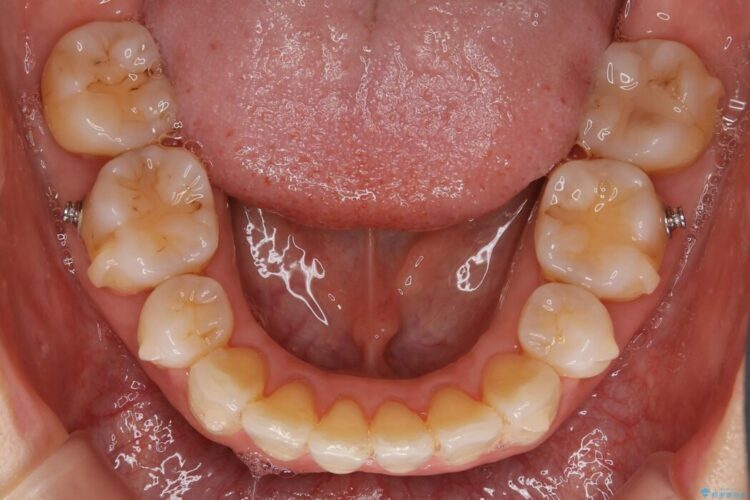

抜歯矯正後の上の前歯の後戻りが気になるとご来院された患者様です。

歯と歯の間を削るのと、歯列のU字型のアーチを僅かに外側に広げる事でスペースを作り、前歯の角度の改善をしました。